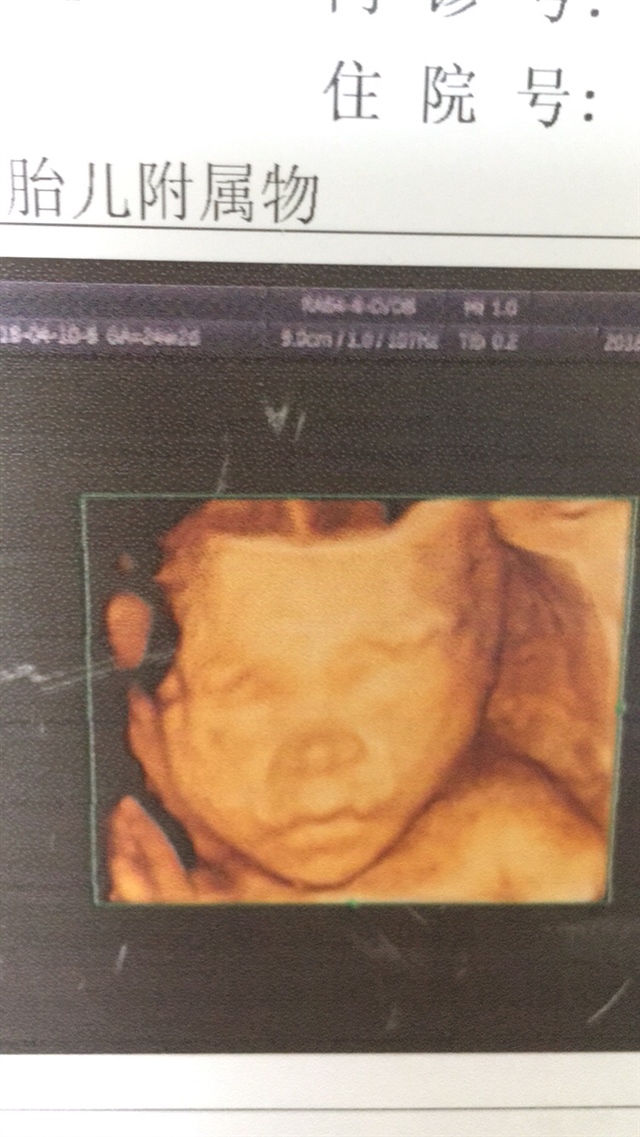

怀孕用户SNGJ

孕19周+3天